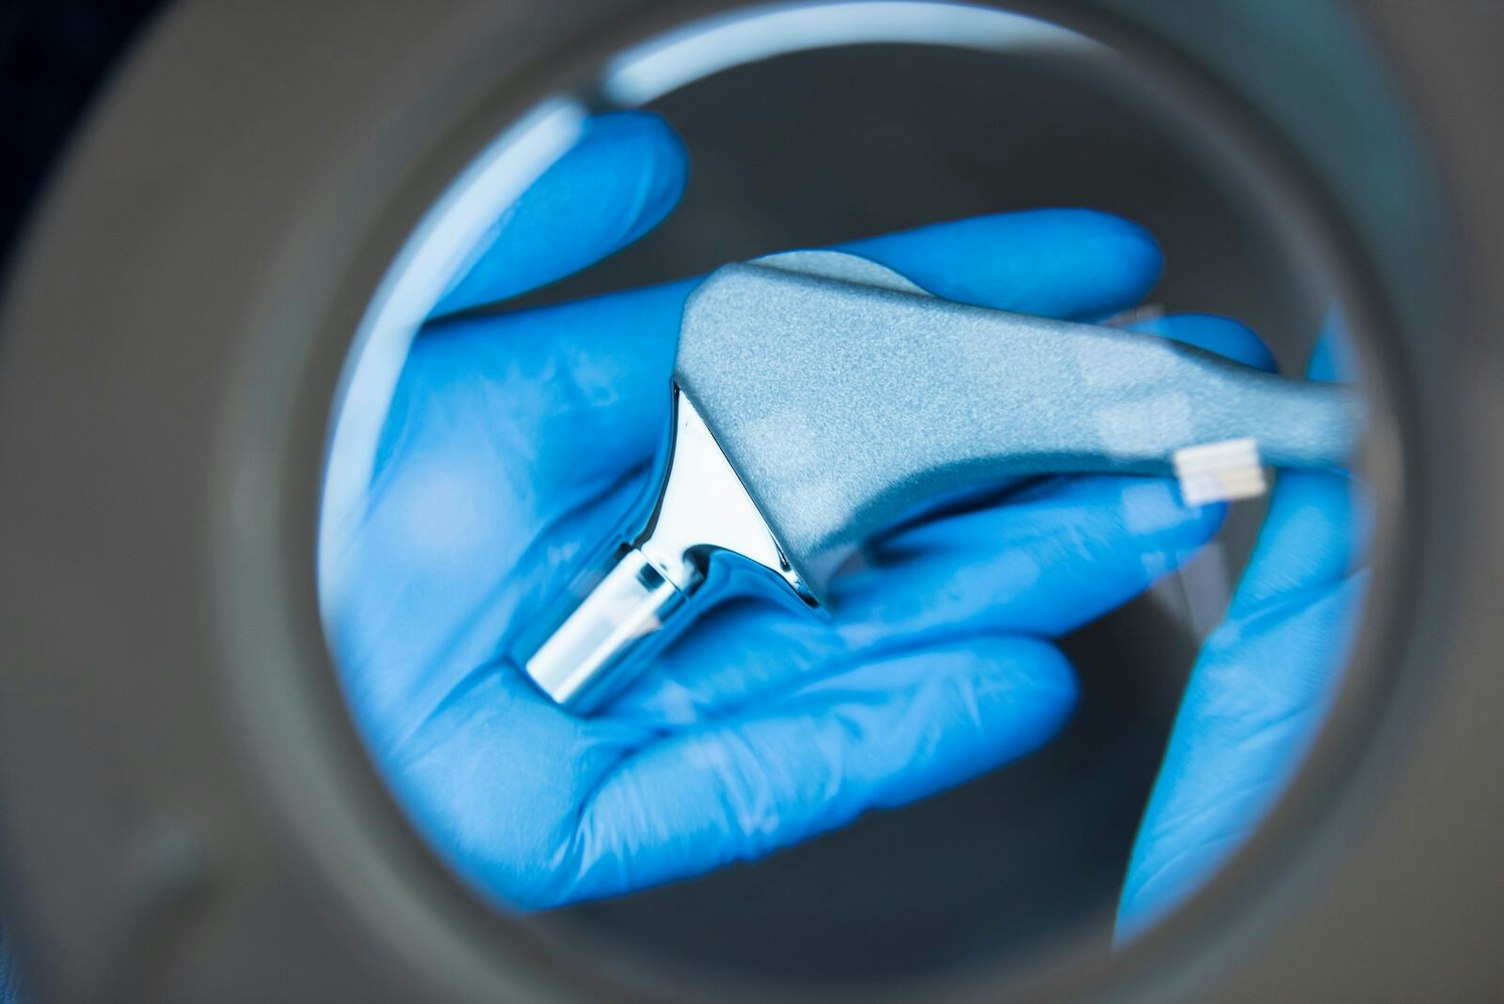

- MDN 1102: non-active osteo- and orthopedic implants. These include:

- Joint (hip, knee shoulder, ankle) and spinal disc replacements